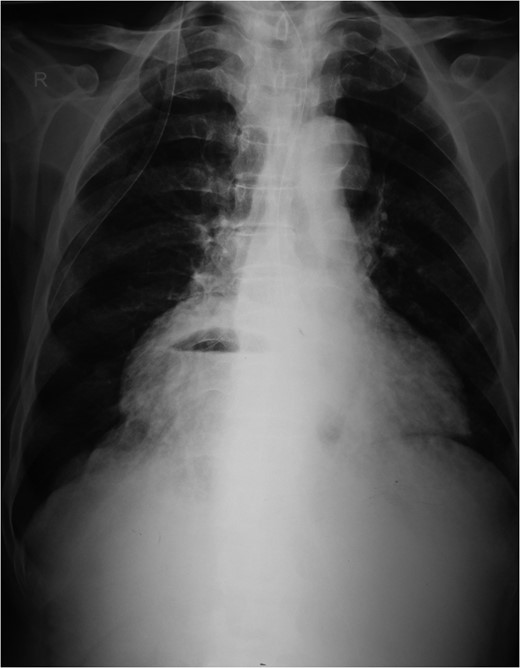

An 80-year-old man presented to our emergency room with multiple episodes of non-bilious vomiting for 4 days and not-passing stool or flatus for 2 days. He also complained of intermittent pain in the upper abdomen, which was not associated with fever, chest pain, melena or diarrhea in the recent past. However, he complained of increased cough and shortness of breath for the last 4 days on the background of a diagnosed chronic obstructive pulmonary disease. There were no similar complaints in the past. On examination, his vital parameters were normal, other than an oxygen saturation of 82% for which oxygen had to be given via face mask. His abdominal examination revealed epigastric fullness with tenderness in the epigastric and right hypochondrium. There was no evidence of peritonitis. Laboratory investigations revealed hypokalemia (3.1 mEq/l) with other parameters being normal. On the chest X-ray obtained, we saw air–fluid levels in the right thoracic cavity (Fig. 1). Computed tomography (CT) scan of the abdomen performed demonstrated a right anterior diaphragmatic hernia with stomach as content. (Figs 2 and 3) The patient was taken to the operating room, and an upper midline laparotomy was performed. Findings included an ~4 × 3 cm defect to the right of the sternum in the anterior diaphragm (Fig. 4), with incarcerated pylorus/antrum of stomach as contents and a grossly distended stomach. Rest of the bowel was normal. The contents were reduced, and the defect closed primarily with 2-0 non-absorbable interrupted mattress sutures (Fig. 5). Postoperative period was uneventful, and chest X-ray revealed a corrected defect with reduced contents (Fig. 6). The patient was started orally on the first postoperative day and discharged on the sixth postoperative day.